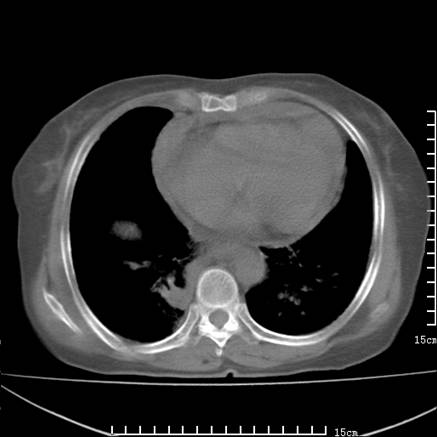

女,王某,58岁,咳嗽三个月余,基层医院二个月前诊为肺结核,用抗结核药二个月无明显疗效。

心包积液致肺瘀血.右侧周围型肺癌伴肺内转移,中间裂积液,叶间胸膜肥厚.右上肺大泡,右侧胸膜肥厚.

双肺继发型tb,心功能不全并肺淤血、心包、双侧叶间裂积液,肺大泡,右下胸膜肥厚钙化。